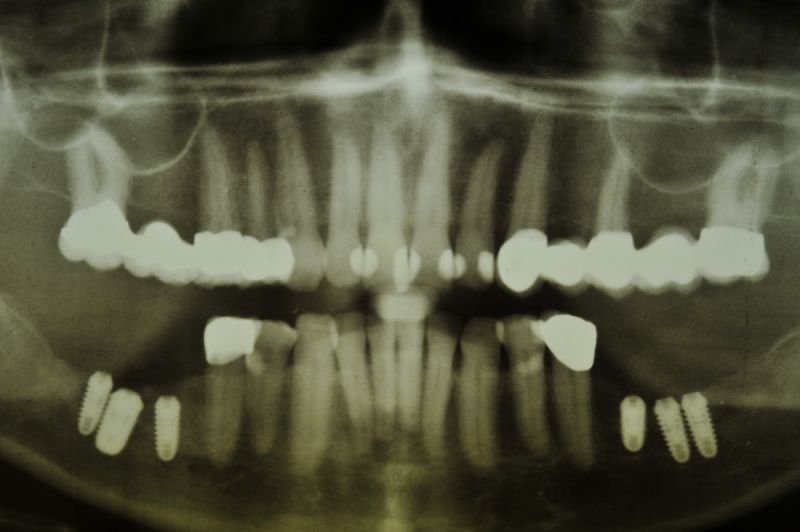

Es war eine Kombination aus Schmerzen bis an die Suizidgrenze, beschränkten wirtschaftlichen Möglichkeiten, sehr stark eingeschränkten Möglichkeiten der für Implantate zur Verfügung stehenden Knochenverhältnisse in einem stark atrophierten Unterkieferseitenzahnbereich und zudem dann auch noch durch auftretenden Problemen bei der Implantatinsertion und nachfolgenden Versorgung der Implantate.

Die Problematik der Implantatversorgungen kann man in einer Analogie folgendermaßen darstellen. Die räumlich beengten Zustände gleichen dem Tanz eines Paares auf einer Briefmarke, und der gleichzeitigen Schritt- und Fusshaltung, dass beim Tanzen die Schuhe geputzt werden können!